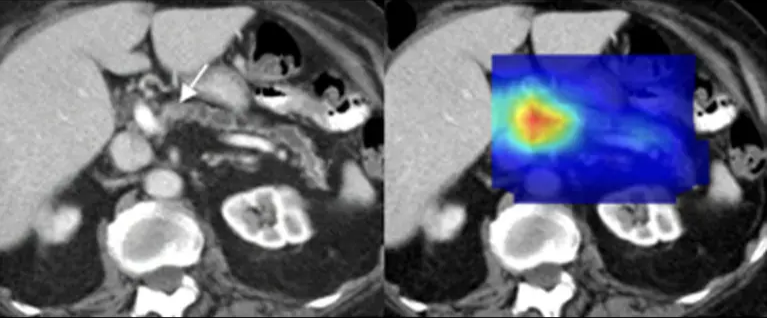

L’imaging radiologico è uno dei settori dove l’intelligenza artificiale ha avuto impatti concreti e immediati. Un gruppo di ricerca guidato dalla Mayo Clinic ha dimostrato che l’AI può individuare segnali precoci di tumore al pancreas su TAC addominali anche fino a 3 anni prima rispetto alla diagnosi clinica standard. Il modello è stato addestrato su decine di migliaia di immagini di pazienti, riuscendo a riconoscere pattern impercettibili all’occhio umano.

Questi sistemi si basano su modelli di deep learning progettati per leggere immagini mediche. In particolare, reti neurali convoluzionali (CNN) 2D e 3D vengono addestrate su grandi dataset di TAC annotate per riconoscere pattern morfologici complessi a livello di pixel, in modo analogo al lavoro di un radiologo ma con una granularità molto più fine. Architetture di tipo U-Net vengono utilizzate per la segmentazione semantica, cioè per isolare automaticamente le aree potenzialmente patologiche. Il risultato non è una semplice classificazione sì/no, ma heatmap integrate nei sistemi PACS che indicano dove il modello concentra la propria attenzione. Le prestazioni vengono valutate con metriche orientate allo screening, come AUC, sensibilità e tasso di falsi negativi, particolarmente critiche quando l’obiettivo è individuare segnali precoci di malattia.